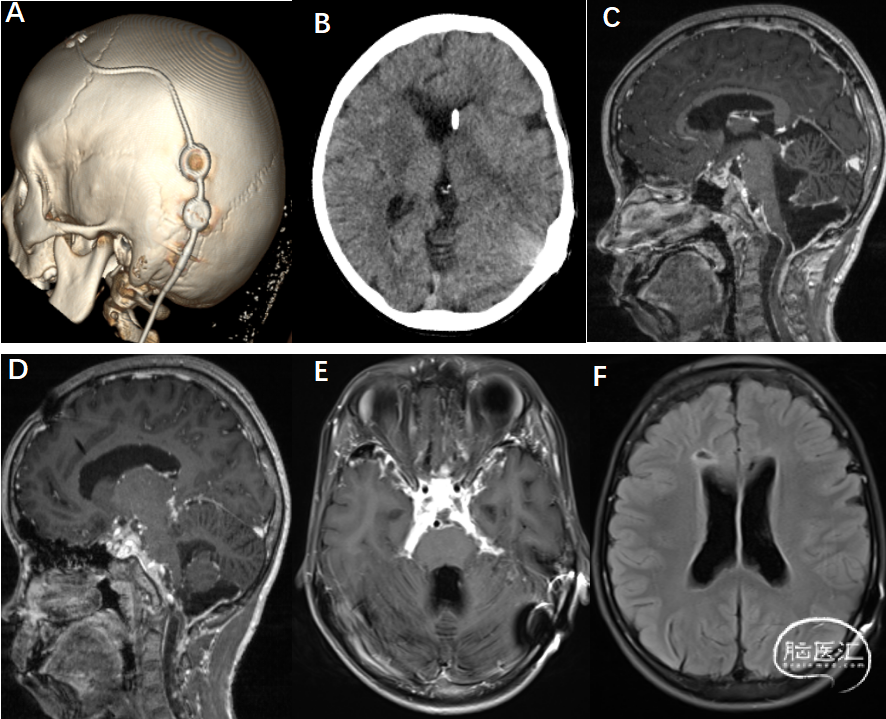

影像资料(2025-9-18):详见下图

A-B: 左侧额部见引流管置入,末端位于左侧脑室;中线结构居中,右侧脑室稍宽

C、D:延髓及颈髓前方见囊状异常信号、T2WI高信号、T2WI FLAIR稍高,DWI信号不高,增强后未见明显强化,颈髓受压后移,颈髓内见条状脑脊液信号B:头颅MR轴位可见幕上脑室明显扩张,脑白质变薄

E:鞍上池及桥前池、枕大池见增强后明显强化

F:右侧额叶T2WI高信号影,脑室系统壁欠光整,附壁见不规整T2WI FLAIR稍高信号